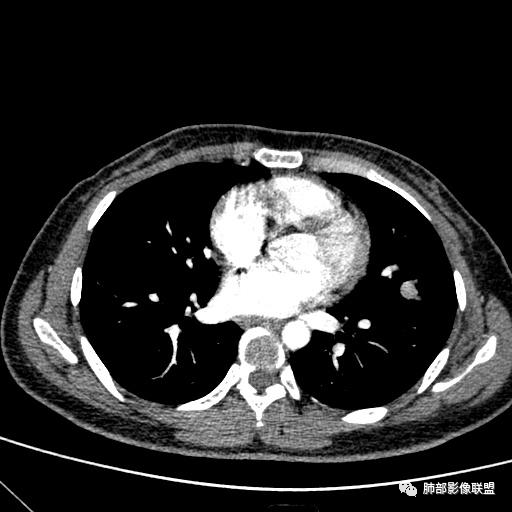

1、临床特点:30岁女性,体检发现肺部结节。

2、影像特点:左肺上叶舌段实性密度结节,边界清楚,略呈不规则三角形,边缘多平直,未见分叶、毛刺及明显收缩。密度均匀,未见钙化、脂肪密度或低密度液化空洞,持续渐进强化。未显示相关支气管及血管出入、血管贴边等。未见明确卫星病灶。双肺门及纵隔未见增大淋巴结。

3、病例小结:年轻女性,体检发现,左肺上叶舌段实性结节,边缘清楚光滑,未见分叶毛刺及收缩,亦未见边界清晰的磨玻璃晕,与支气管血管了无瓜葛等,较为符合的是肺良性结节。

3)边界清楚,未显示相关支气管及血管出入,强化明显,应当想到硬化性肺细胞瘤。

CT:形态:圆形或椭圆形结节,边界清楚,无分叶及毛刺、无胸膜凹陷征及血管集中等恶性征象,无卫星病灶,周围无纹理增多及粘连等;大小:平均直径3cm,从<1cm到>10cm均有报道;密度:均匀、软组织密度,偶有出血、囊变、钙化;强化方式:多为均匀明显强化,少数不均匀强化;其它特殊征象:血管贴边征 、空气半月征 、晕征,偶见纵隔淋巴结肿大。